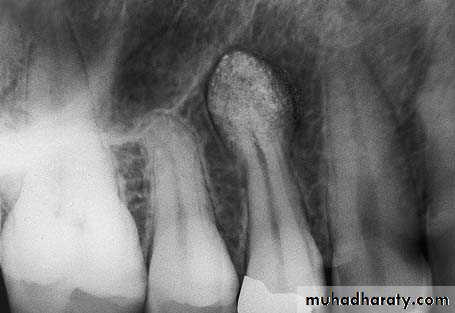

2- Extraction of an Intact Tooth with Hypercementosis of the Root Tip

A/ single rooted toothAn L-shaped incision is made and the flap is reflected. The buccal plate covering the surface of the root is removed, and the tooth is extracted using forceps

1- a mandibular molar with hypercementosis at the distal root tip.

2- Envelope flap is reflected, part of the buccal plate is removed, and the tooth is sectioned buccolingually at the crown as far as the intraradicular bone3- Extraction of the normal part of the root then widening of the alveolus with a round bur, so that removal of the root is possible without fracturing the bulbous root tip. Extraction of the distal portion of the tooth using forceps after creating a pathway for removal